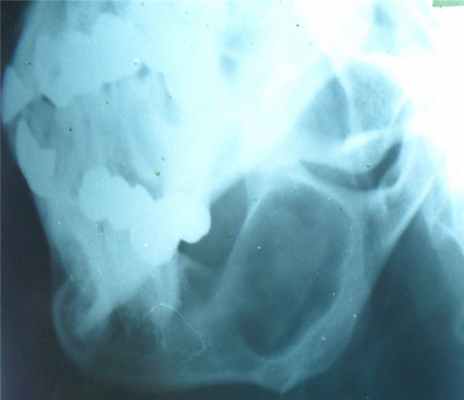

- поражаются фаланги, пястные, плюсневые, реже запястные кости, отростки позвонков, передние концы верхних ребер, тазовый скелет, грудина и весьма редко – длинные трубчатые периферические кости,

- в малых цилиндрических костях хондромы гнездятся в диафизах и эпифизах, в больших трубчатых – только в метафизарных костях,

- как правило хрящевые опухоли множественны и чаще всего наблюдаются в числе одного или нескольких на фалангах рук и пястных костях,

- чаще процесс двусторонний, но не симметричный.

- опухоли шарообразны или овальны, расположены то центрально и вздувают кость изнутри, то эксцентрично и более поверхностно и связаны только с корковым веществом кости,

- опухоль состоит из прозрачного, хрящевого фона на котором видны островки, точечки из извести или костного вещества,

- наружные контуры гладкие и при доброкачественном течении не прерываются,

- на месте слияния опухолевых шаров костная перегородка иногда толстая, в других случаях истончена или отсутствует,

- при поражении эпифизарных хрящей приходится видеть торможение роста кости в длину или ее искривлении,

- нередко центрально расположенная хондрома осложняется патологическим переломом,

- корковый слой неравномерен и местами утолщен,

- при хондроме поверхность кости шероховата.